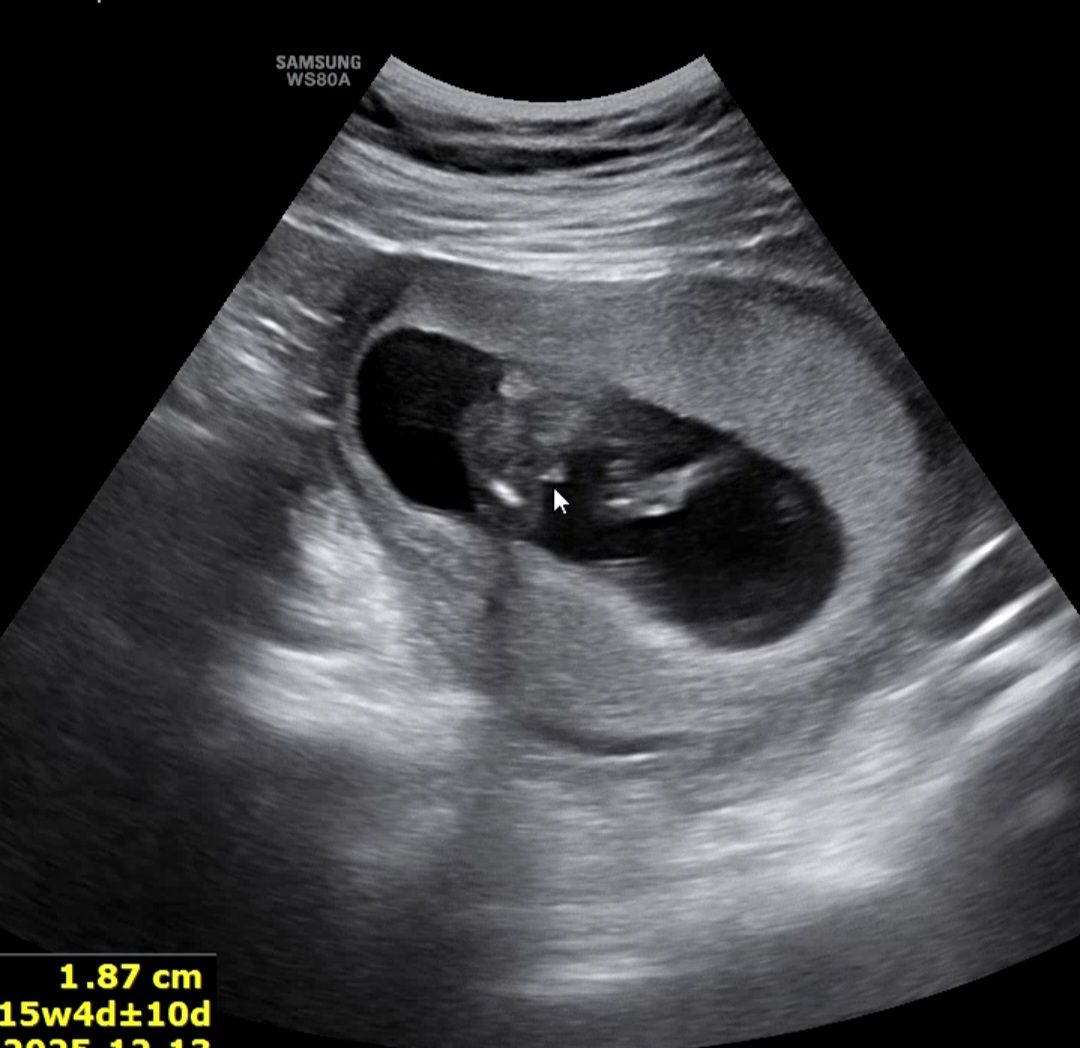

🌶확정일까요 반전은없을까요 ㅎ

네, 삼각점이에요!

네 이건 포기하세요.. 저도 그렇게 아들만 둘이에요ㅠ